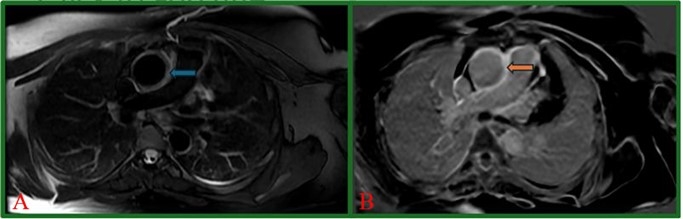

A healthy 42-year-old woman with a BRCA mutation presented for breast cancer screening via a magnetic resonance imaging (MRI). This revealed cardiomegaly, for which she was referred to our hospital for workup. Her exam revealed a widened pulse pressure (70 mmHg) and a diastolic murmur at the right upper sternal border. Subsequently, a computed tomography (CT) and transthoracic echocardiogram showed perivascular fat-stranding concerning for aortitis (Figure 1A) and aortic regurgitation (AR) with left ventricular (LV) dilation and dysfunction, respectively. These findings were confirmed with a cardiac MRI (Figure 2) and transesophageal echo. Subsequent coronary CT angiogram ruled out aortic dissection but revealed 70% ostial left main (LM) coronary artery stenosis (Figure 1B), which was confirmed on coronary angiogram (Figure 3A).